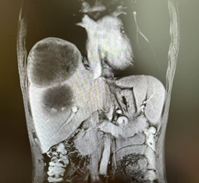

新辅助(两次HAIC和两个周期靶免治疗)后CT

由于病人一般情况较好,肝功能良好(Child-pugh A级),经多学科会诊临床确认肿瘤为IIb期肝细胞癌,属于可切除性肝癌,但存在高危复发因素,建议先行新辅助治疗后手术切除。经两次肝动脉关注化疗(HAIC)(奥沙利铂+5-Fu+亚叶酸钙方案)和两个周期的靶向免疫治疗(仑伐替尼+帕博利珠单抗方案),第二次介入造影是肿瘤血供不明显,第二次介入治疗4周后复查CT提示肿瘤缩小不明显但坏死征象明显,经MRI证实仍有少许血供,于是经多学科会诊后决定行前入路右半肝切除术。